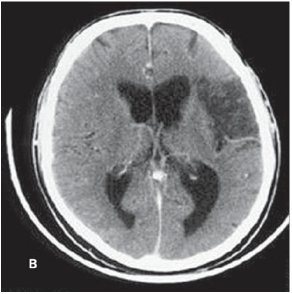

Paciente masculino, 65 anos, apresenta-se ao serviço de urgência/emergência com quadro de início súbito de disartria e perda de força em dimídio direito, com 2 horas de evolução. Ao exame neurológico, evidenciouse as seguintes alterações: hemianopsia homônima direita, força motora em membro superior direito grau 3/5 e em membro inferior direito grau 4+/5, e redução da sensibilidade em dimídio direito, principalmente em membro superior direito. A tomografia de crânio realizada durante a internação está demonstrada a seguir. Diante do quadro exposto, assinale a alternativa correta.